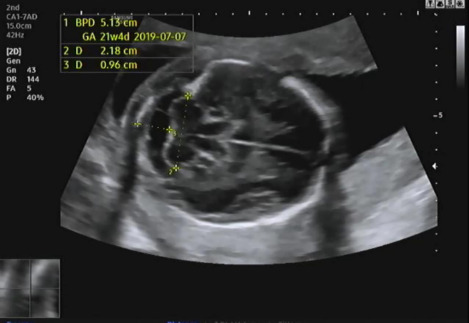

그다음 태아의 머리 둘레를 측정하고 21주 차에 맞게 뇌가 주수에 알맞게 발달하였는지, 물혹 등의 여부나 기형이 있는지 확인을 한다.